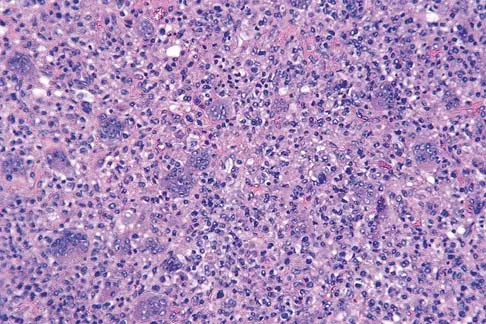

Question 14

Figures 19a and 19b show the AP and lateral radiographs of an 18-year-old man who has had knee pain for 3 months. Figure 19c shows a histopathologic photomicrograph of the biopsy specimen. Which of the following factors is most likely to affect his survival?

Explanation